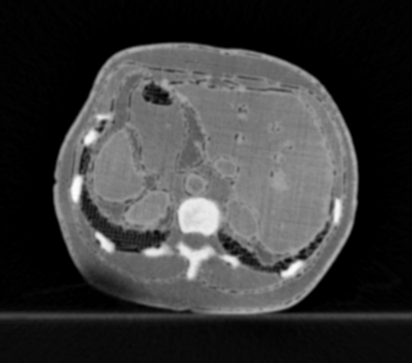

3.1.3 Example 2: data driven reconstruction methods in lung CT screening

There is sufficient evidence that screening for certain tumours using CT images may improve prognosis of cancer survivability (citep \@BBN(Boiselle, 2013)). As mentioned above, in order to gain better image quality with less X-ray dose, many enhanced regularization techniques with integrated machine learning steps have been suggested for CT reconstruction, and in a full reference setting they are commonly evaluated by applying PSNR and SSIM, see e.g. (citep \@BBN(Adler and Öktem, 2018; Hendriksen, Pelt, and Batenburg, 2020; Unal, Ertas, and Yildirim, 2021)). As CT images are generally taken to perform a clinical task, they are not the final step of a medical process but often the initial one. Therefore the definition of what makes a good image heavily depends on the task in hand, and for prognosis related cancer the identification of tumours is of upmost importance.

In on-going research on photon counting detector types and screening procedures for lung cancer (EPSCR grant: EP/W004445/1) an experiment was conducted testing enhanced reconstruction algorithms. Simulations using less than 10% of a clinical X-ray dose were performed to investigate if data-driven methods could sufficiently enhance the images to clearly see the tumours in the lungs while providing very low amount of dosage to the patients. The corresponding data was a CT-dose simulation, using images from the open LIDC-IDRI dataset (citep \@BBN(Armato et al., 2011)) as references, as well as simulated and reconstructed images with in-house software. Figure 3 shows the results of the experiment. We show the reference image used as basis for the simulation, together with five different reconstruction algorithms. The first is an iterative solver, a gradient descend algorithm with TV minimization (citep \@BBN(Sidky et al., 2012)) and (c)-(f) correspond to machine learning methods: FBPConvnet is a denoising algorithm that cleans the bad image (citep \@BBN(Jin et al., 2017)), LPD is an iterative unrolled method that combines traditional solvers with machine learning (citep \@BBN(Adler and Öktem, 2018)), Noise2Inverse is a self-supervised learning method (i.e. does not require ground truth data) (citep \@BBN(Hendriksen et al., 2020)) and ItNet is another iterative unrolled method, the best performing winner of the AAPM DL-Sparse-View CT challenge (citep \@BBN(Genzel, Macdonald, and März, 2021)). ItNet is also judged here as the best result according to PSNR, SSIM and LPIPS.

Refer to caption

(a) Reference

(b) (27.6, 0.70, 0.37)

(c) (31.9, 0.73, 0.29)

(d) (32.5, 0.84, 0.19)

(e) (32.5,0.77, 0.20)

(f) (33.0, 0.89, 0.12)

Figure 3: Reference image (a) and outputs of different reconstruction methods (b)-(f) applied to dose simulated data. PSNR/SSIM/LPIPS are unable to identify the best reconstruction (c), where also the tumour is visualized well.

FR-IQA mismatches

This experiment was performed to evaluate the quality of different kinds of CT reconstruction, and especially the lung tumour detection capabilities thereof. The best result according to the chosen IQA measures is given by ItNet in Figure 3(f), which performs visually poorly. Not only the tumour (zoomed in white circle) is significantly less visible in the reconstruction, but ItNet also produces structures in the lung that are different than the ones in the reference image; it blurs and lengthens much of the soft tissue present in the lungs and it also created structure from noise in some places. Moreover, the image is overly smooth. Comparing the other reconstruction algorithms, it seems that FBPConvnet Figure 3(c) is the one performing best at preserving the shape of the lung nodule, even when the resulting image contains enhanced pixel-level noise.

We can see here that the qualitative findings strongly contradict the numbers provided by the selected measures. The reconstruction of ItNet, Figure 3(f), is outperforming the other reconstructions in regards of the measures, and the qualitative winner FBPConvnet, Figure 3(c), is judged as second worst by the same measures. This experiment suggests that the discussed measures are not a good choice for that kind of CT reconstruction applications and are yielding misleading results.

While pixel-independent random noise may be a worse effect in a natural image than a slightly oversmooth reconstruction, this is not true in CT images, where small structures may disappear if smoothing is promoted against edge preservation. In iterative reconstruction algorithms such choices are explicitly made by choosing the prior appropriately, in data-driven models the researcher has limited control on the type of implicit priors the algorithm learns from the data, i.e. model builders do not know what the algorithms chooses to learn from the ground truth. In these cases appropriate evaluation would therefore be even more important to ensure quality. If this is followed by a blind evaluation using non-appropriate metrics, the promotion of less desirable images can happen, chosen by an implicit assumption on the metric rather than the actual goal of the task.